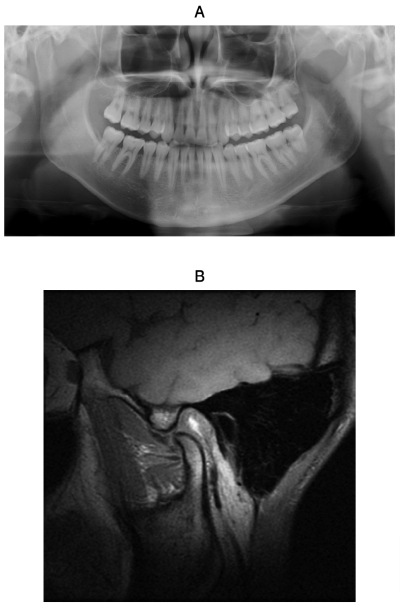

23歳の男性。開口障害を主訴として来院した。1年前から開閉口時に左側顎関節に雑音があり、2日前から急に口が開かなくなったという。右側顎関節に異常は認められない。初診時のエックス線写真と開口時の左側顎関節のMRIを示す。

開口障害の原因はどれか。1つ選べ。

d. 関節円板の前方転位